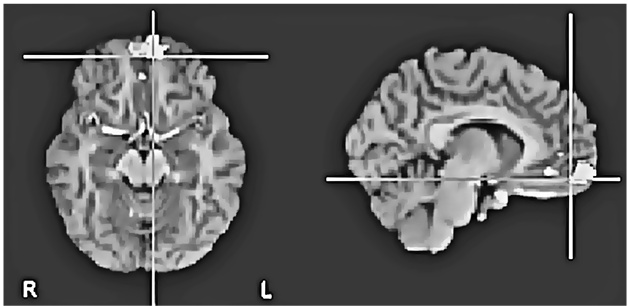

Но это было еще не все. Харрис обнаружил, что оценка «верю» сопровождалась усилением активности в вентромедиальной префронтальной коре (рис. 8.1a ниже) – участке мозга, отвечающем за совмещение факта и эмоции и изменение поведения в ответ на изменение обстоятельств (другими словами, уравновешивание «за» и «против»). «Не верю», в свою очередь, активизировала переднюю островковую долю мозга (рис. 8.1b) – участвующую в том числе и в кодировании негативных реакций, таких как боль и отвращение, и в оценке приятности различных вкусов и ароматов.

Рис. 8.1a. Усиление активности в вентромедиальной префронтальной коре в ответ на правдивые утверждения («верю»), относящиеся к семи разным тематическим категориям (математика, география, автобиография, религия, этика, семантика и события) (по материалам Харриса и др., 2008)